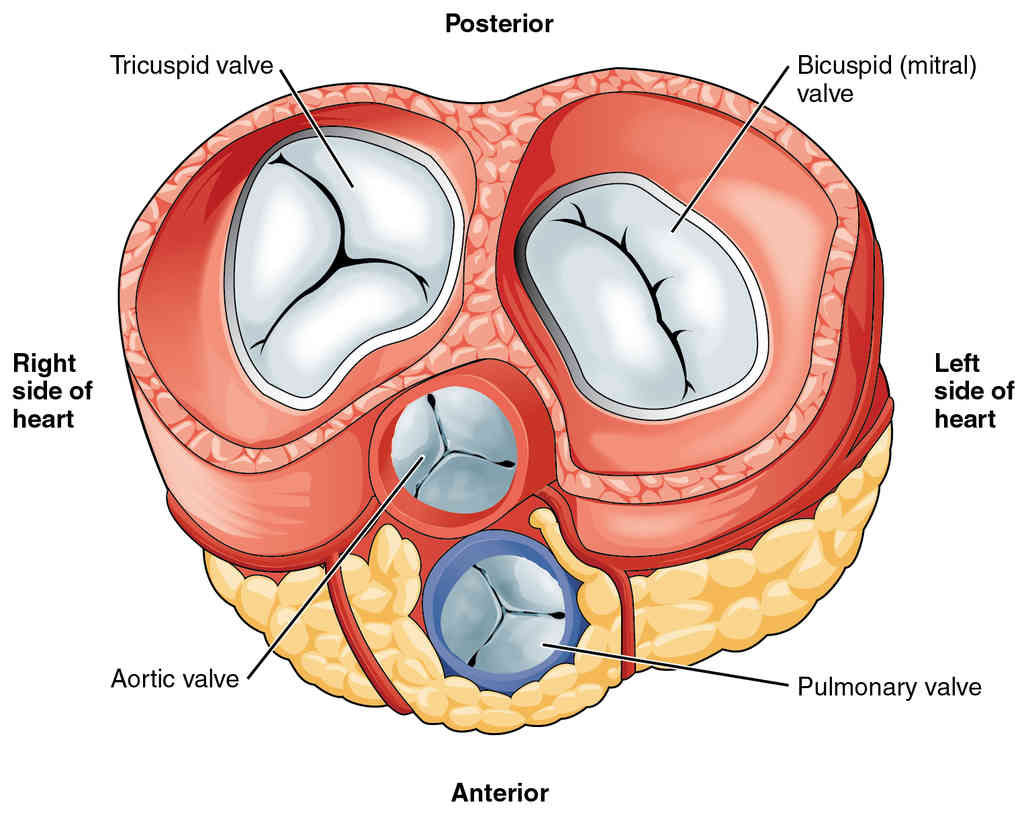

This page is under construction. For now, it is just a resource of the images found in the OpenStax Anatomy and Physiology Handbook. It wil slowly change into a revision tool. Each slide has a number. Use this to refer to the slide. When completed, it will have an unlabelled section, with labelled slides in parallel. On the unlabelled slides, write your answer and use the labelled slide to assess yourself. Keep track by also noting the number on each slide. Improvement at each attempt is important, more so than full marks on a first attempt.